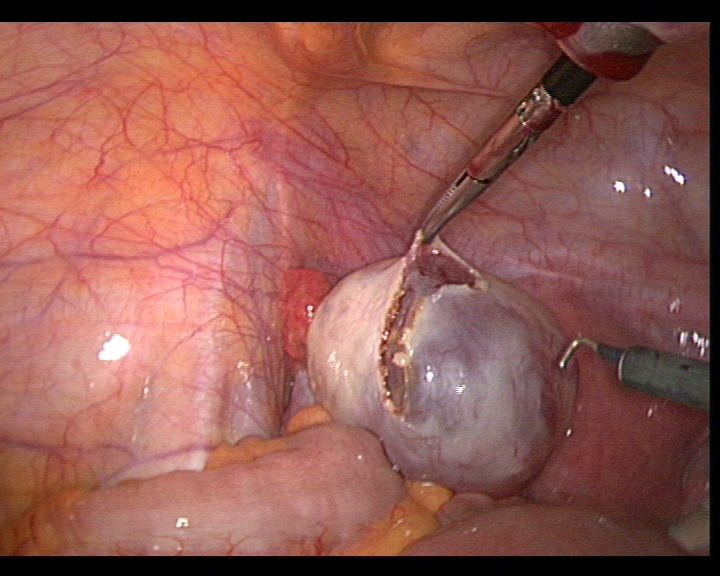

患者35岁,G4P0,2011年4月因继发不孕、月经减少2年,行宫腔镜探查,发现宫腔广泛重度粘连,单极电切分粘,恢复宫腔形态,显露双侧输卵管开口,放置节育环一个,术后月经恢复正常。2011年9月行宫腔镜二探并取环,O型环部分嵌顿,分离残留粘连,宫腔形态正常,双侧输卵管开口可见,同时行腹腔镜下左侧卵巢囊肿剥除术,术中通液双侧输卵管通畅。术后病人及爱人外出旅行,2个月后自然妊娠至足月,2012年7月要求我到其住院医院为其剖宫产,胎盘粘连,出血较多,手术顺利。现49岁,G5P1。